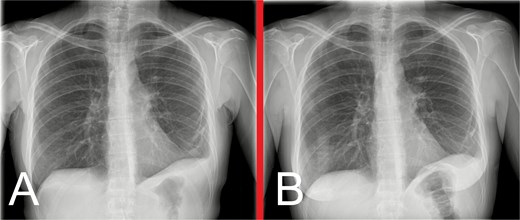

She remained well on outpatient follow-up at 2 weeks. Progress CXRs at 3 and 7 months showed satisfactory appearances, without evidence of hernia recurrence (Fig. 6).

Progress anteroposterior view CXRs taken at (A) 3 months and (B) 7 months postoperatively, showing persistent, but stable, left hemidiaphragm elevation with associated generalized volume loss of the left lung, but no evidence of hernia recurrence.